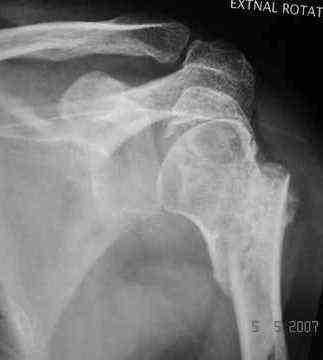

Dear all, A heavy built 30-year-old male patient sustained fracture dislocation of left shoulder about 8 months back.

He has 60* elevation…primarily it is scapulothoracic motion. External rotation at side is minus 30*.

Movements are painful.

Looking at his previous x-rays, I was thinking of refixing the greater tuberosity, however got anaxillary view done today which was never done during this period and this shows non-union.

It looks like the initial injury was a head splitting fracture. Presently the patient has a non-union at the level of the anatomical neck with displaced tuberosities. I would tackle the non-union, and would try to replace the tuberosities, a difficult procedure. I would use the proximal humerus locking plate from the AO.